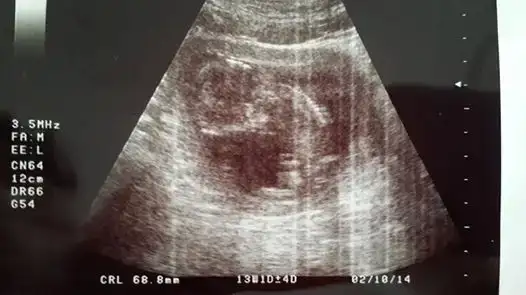

ya kızlar benim iki hafata önceki ultrasonum var belli midir? dr erkek muhtemelen dedi ama kesin demedi. yeni ultrasonu ekleyemedim bir türlü ışık patlaması oluyor. çocuğun kafası kocaman görüyodu korktum ya siiznkilerde de öyle oldu mu? kötü bişey olsa dr söylerdi dimi? ya da ultrasn eski diye mi öyle çıktı?

Eki Görüntüle 1016536 Eki Görüntüle 1016536